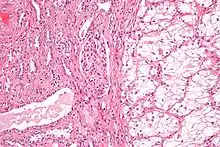

| Micrograph of the most common type of renal cell carcinoma (clear cell)—on right of the image; non-tumour kidney is on the left of the image. Nephrectomy specimen. H&E stain | |

Histopathology

The gross and microscopic appearance of renal cell carcinomas is highly variable. The renal cell carcinoma may present reddened areas where blood vessels have bled, and cysts containing watery fluids.[58] The body of the tumour shows large blood vessels that have walls composed of cancerous cells. Gross examination often shows a yellowish, multilobulated tumor in the renal cortex, which frequently contains zones of necrosis, haemorrhage and scarring. In a microscopic context, there are four major histologic subtypes of renal cell cancer: clear cell (conventional RCC, 75%), papillary (15%), chromophobic (5%), and collecting duct (2%). Sarcomatoid changes (morphology and patterns of IHC that mimic sarcoma, spindle cells) can be observed within any RCC subtype and are associated with more aggressive clinical course and worse prognosis. Under light microscopy, these tumour cells can exhibit papillae, tubules or nests, and are quite large, atypical, and polygonal.

Recent studies have brought attention to the close association of the type of cancerous cells to the aggressiveness of the condition. Some studies suggest that these cancerous cells accumulate glycogen and lipids, their cytoplasm appear "clear", the nuclei remain in the middle of the cells, and the cellular membrane is evident.[59] Some cells may be smaller, with eosinophilic cytoplasm, resembling normal tubular cells. The stroma is reduced, but well vascularised. The tumour compresses the surrounding parenchyma, producing a pseudocapsule.[60]

The most common cell type exhibited by renal cell carcinoma is the clear cell, which is named by the dissolving of the cells' high lipid content in the cytoplasm. The clear cells are thought to be the least likely to spread and usually respond more favourably to treatment. However, most of the tumours contain a mixture of cells. The most aggressive stage of renal cancer is believed to be the one in which the tumour is mixed, containing both clear and granular cells.[61]